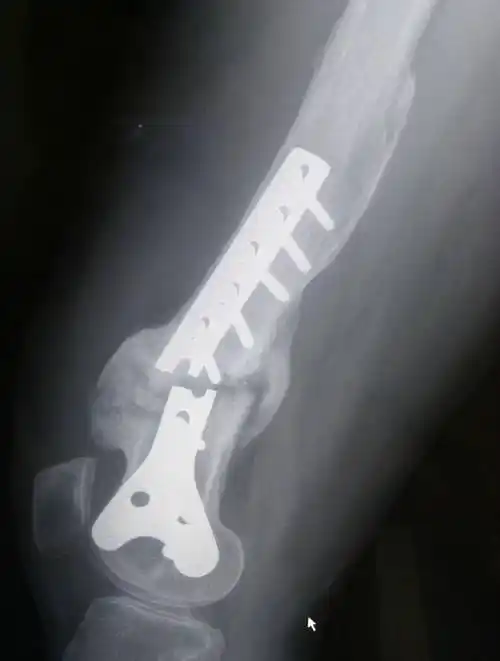

骨折以后上钢板螺钉固定是很常见的